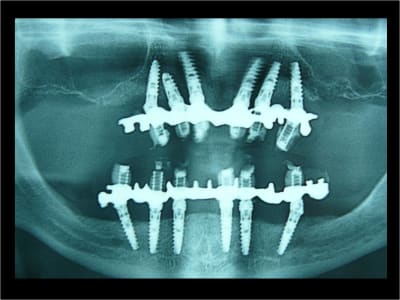

Pano de contrôle

> 2 ANS après MCI Bimaxillaire en 1 intervantion

Depuis + de 10 ans Positdental a développé des solutions technique pour indexer le pilier prothétiques lorsque l'implant est angulé, une des réalisations en 2008.